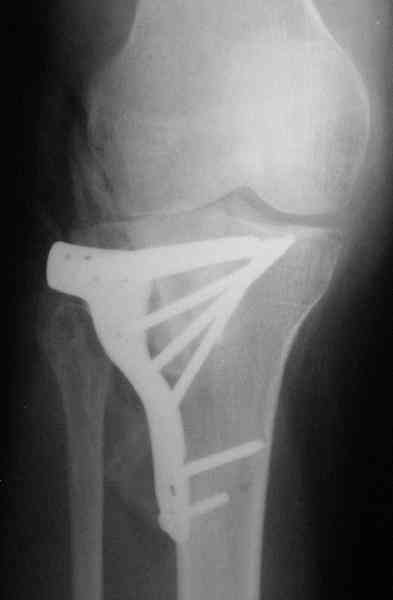

Abdurashid Turaev 24 Апрель 2008, 00:19

Уважаемые коллеги , друзья! всем большое спасибо! Очень интересные высококвалифицированные предложения, действительно этот форум для нас практических врачей как школа повышения квалификации и в конечном счете грамотное лечение больного Ч Е Л О В Е К А.

Наш план; доступ как подсказал Michael, по возможности репозиция, костная аутопластика дефекта метафиза, винты и спицы, АВФ и умеренная дистракция с шарнирными стержнями, и ранная пассивная разработка. Операцию планируем на следуюшей недели.